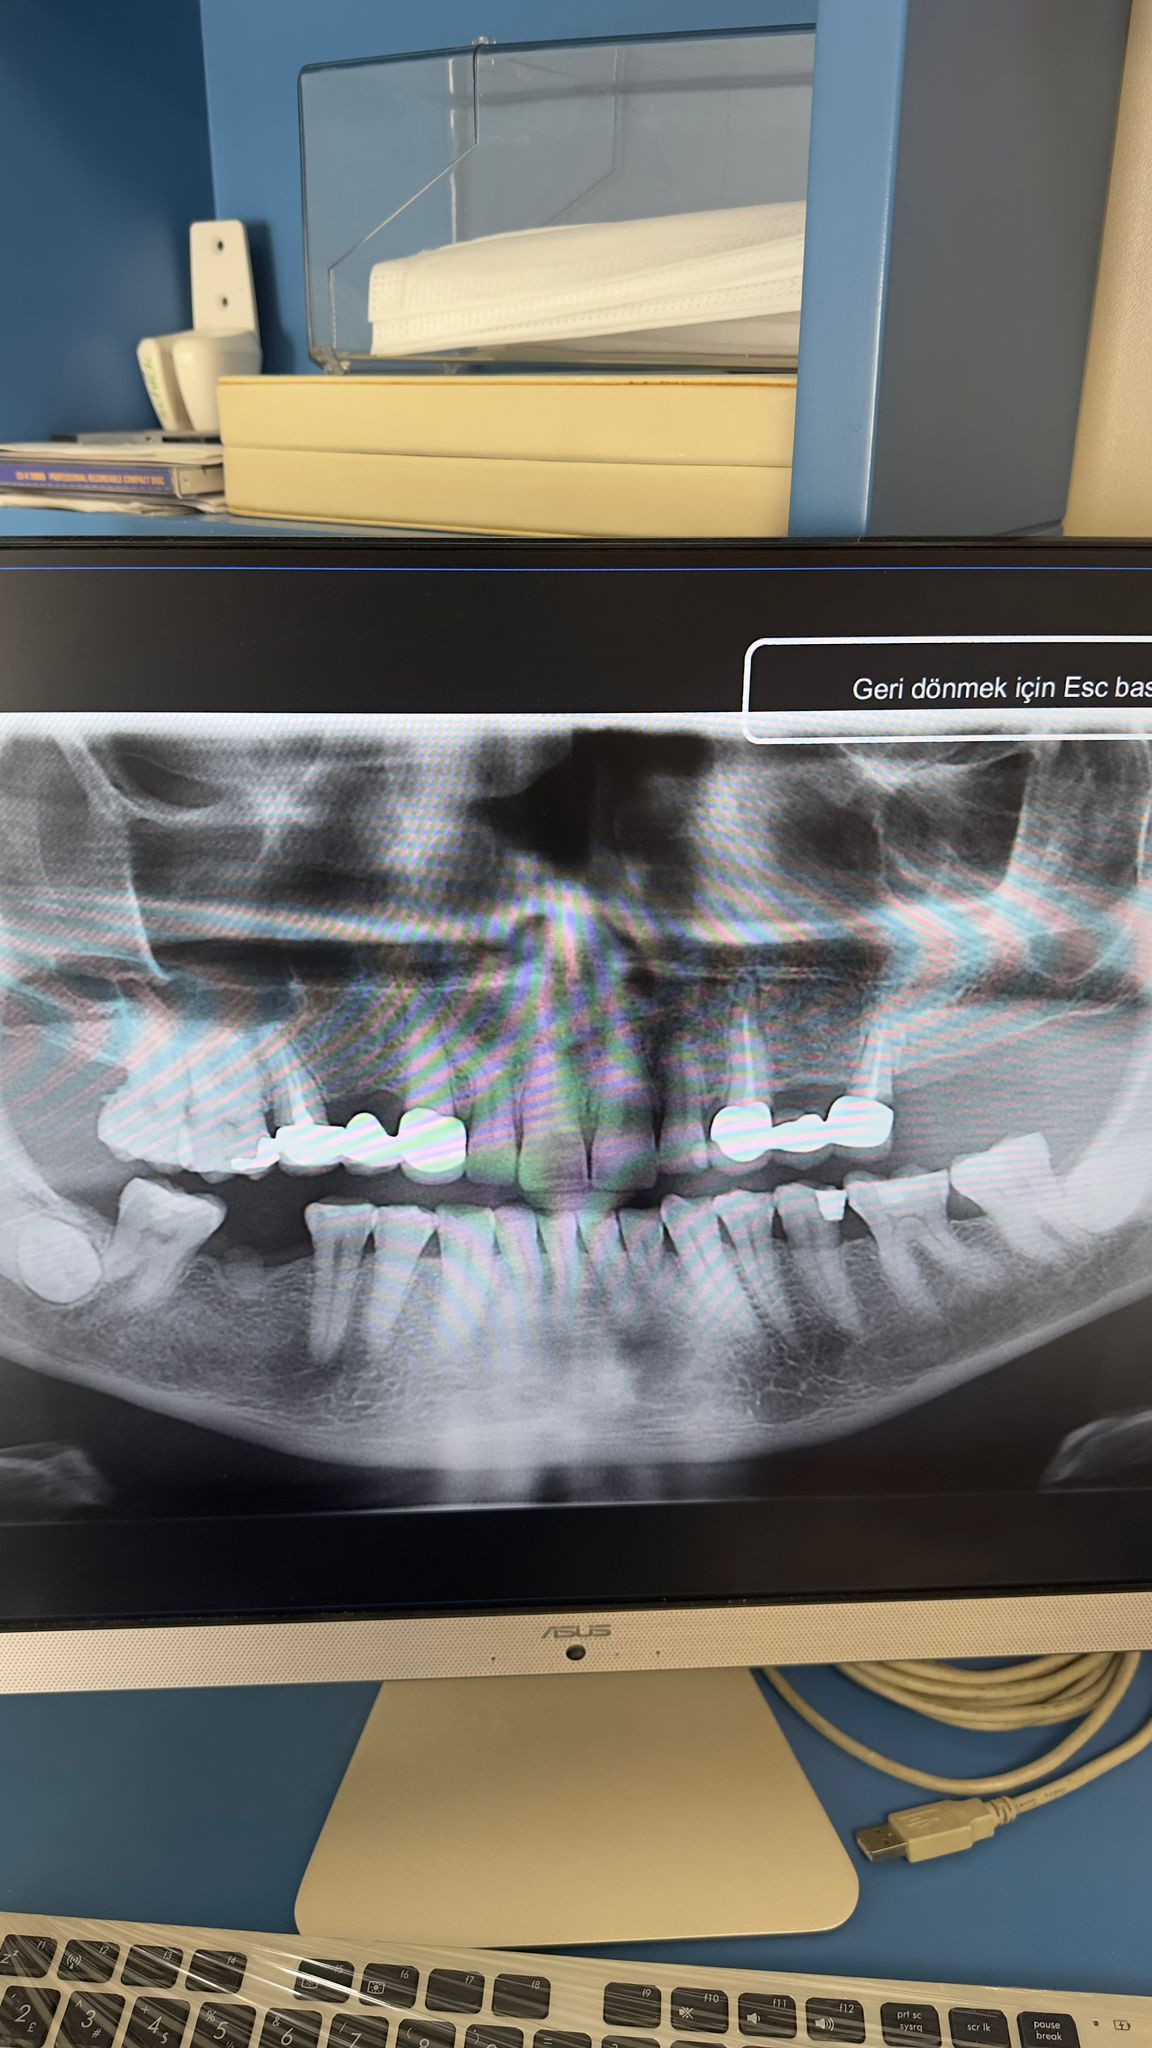

Ahmet Doğan ( 15.10.1972)

Hastanın sağ üst ve alt 1. büyük azı dişlerinin eksik olduğu tespit edilmiştir. Gerekli muayene ve tetkikler yapıldıktan sonra sağ üste 3.7 mm, sağ alta 4 mm çapında iki implant yerleştirilmiştir. Osteointegrasyon için beklenmektedir. 29 Eylül muayene 13 Ocak implantlar yerleştirildi.